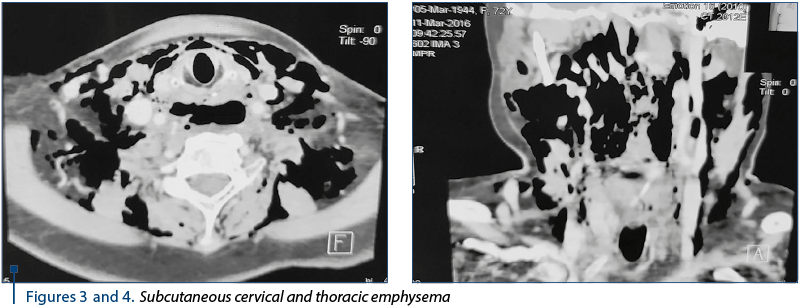

The urgent CT scan (2773/11.03.2016) revealed the diffuse thickening of the upper cervical and thoracic eso­phagus wall, with the delimitation of a fluid, inhomogeneous, diffusely delimited area with hydroaeric (Figures 1 and 2), cervical inferior and superior mediastinal visual (C5-T4) displayed posterolateral as it compressed the eso­phagus and partly the posterior wall of the trachea. Diffuse perilaryngeal infiltration with diminishing the laryngeal lumen, the infracentimetric hyper density zone of the suspected cervical inferior body (C7) anterolateral left in relation to esophageal wall; subcutaneous emphysema is marked on the cervical, thoracic and middles and posterior mediastinal level in the upper third (Figures 3 and 4). Bilateral pleural fluid. No changes in pulmonary transparency.

Figures 3 and 4. Subcutaneous cervical and thoracic emphysema